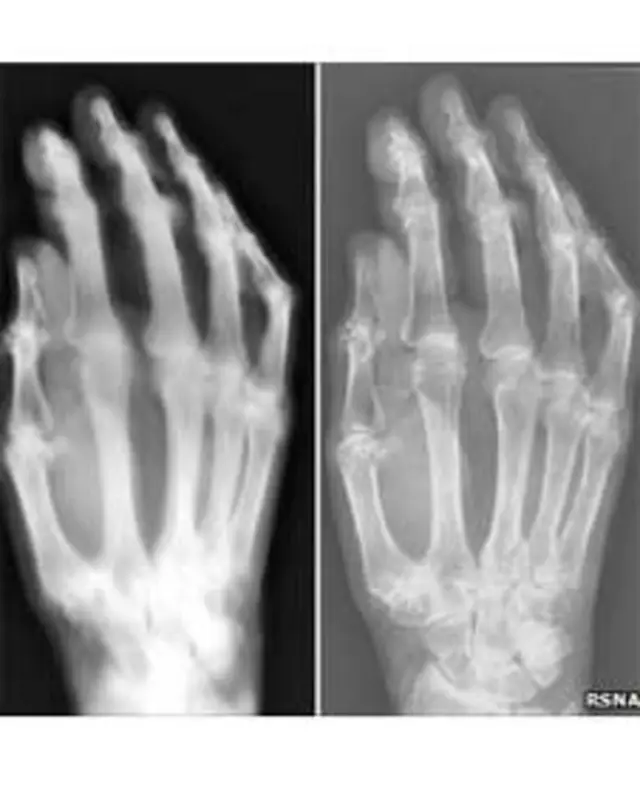

Los investigadores, que provienen del mismo pueblo de Holanda donde fue fabricada la máquina, la usaron para producir unas impresionantes imágenes que no parecen corresponderse con su edad y simplicidad.

Teniendo en cuenta que se podía necesitar una dosis de radiación alta para llevar a cabo las pruebas, el equipo usó la mano de un cadáver como objeto de estudio, en lugar de la "mano de señorita" que figura en las notas de Hoffmans y Van Kleef.

En ese sentido, el equipo usó un detector moderno y vio que con el sistema anticuado se necesitaba una dosis de radiación 10 veces más alta que con uno moderno.

Usando una placa fotográfica y las mismas condiciones que usaron Hoffmans y Van Kleef, se necesitaba una dosis 1.500 veces más alta.

Es más: los rayos X se salieron de la máquina y alcanzaron un área amplia, dando lugar a imágenes borrosas.